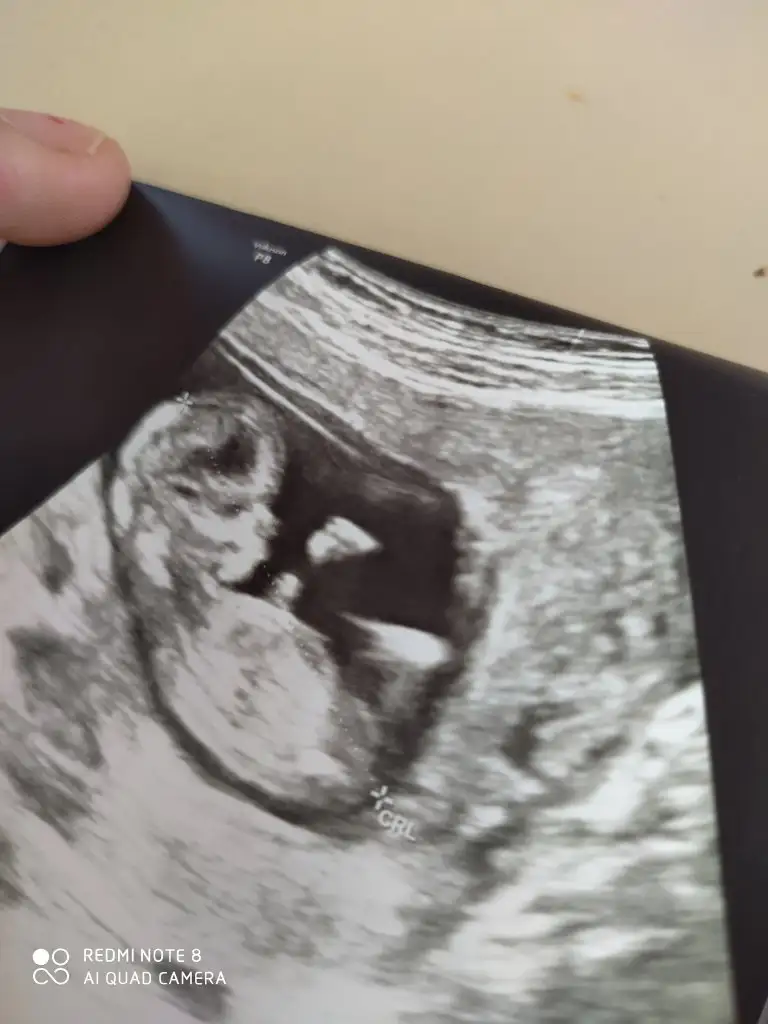

Şimdi tam hali var şükürKafası vartam halı yokmu bebegin

Sanki erkek gibiŞimdi tam hali var şükür

teşekkür ederim kafa yapısı kız gibi ama di mi?Sanki erkek gibi